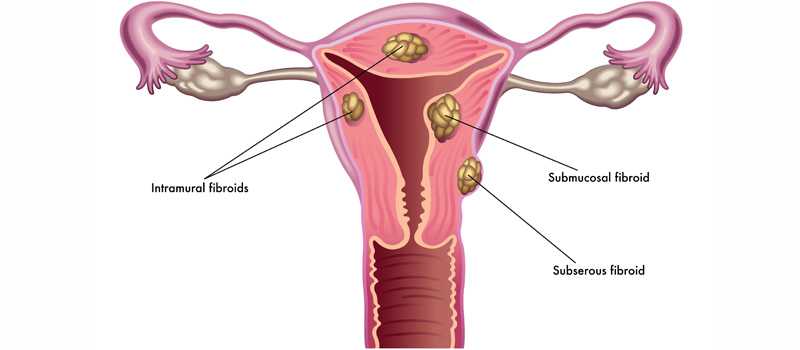

• Fibroids are abnormal growths that develop in or on a woman’s uterus. Sometimes these tumors become quite large and cause severe abdominal pain and heavy periods. In other cases, they cause no signs or symptoms at all. The growths are typically benign, or noncancerous. The cause of fibroids is unknown.

What are the different types of fibroids?

The type of fibroid a woman develops depends on its location in or on the uterus.

• Intramural fibroids

Intramural fibroids are the most common type of fibroid. These types appear within the muscular wall of the uterus. Intramural fibroids may grow larger and can stretch your womb.

• Subserosal fibroids

Subserosal fibroids form on the outside of your uterus, which is called the serosa. They may grow large enough to make your womb appear bigger on one side.

• Pedunculated fibroids

Subserosal tumors can develop a stem, a slender base that supports the tumor. When they do, they’re known as pedunculated fibroids.

• Submucosal fibroids

These types of tumors develop in the middle muscle layer, or myometrium, of your uterus. Submucosal tumors aren’t as common as the other types.

o Fibroids - these benign (not cancerous) growths in the muscular wall of the uterus are a common cause of heavy bleeding.